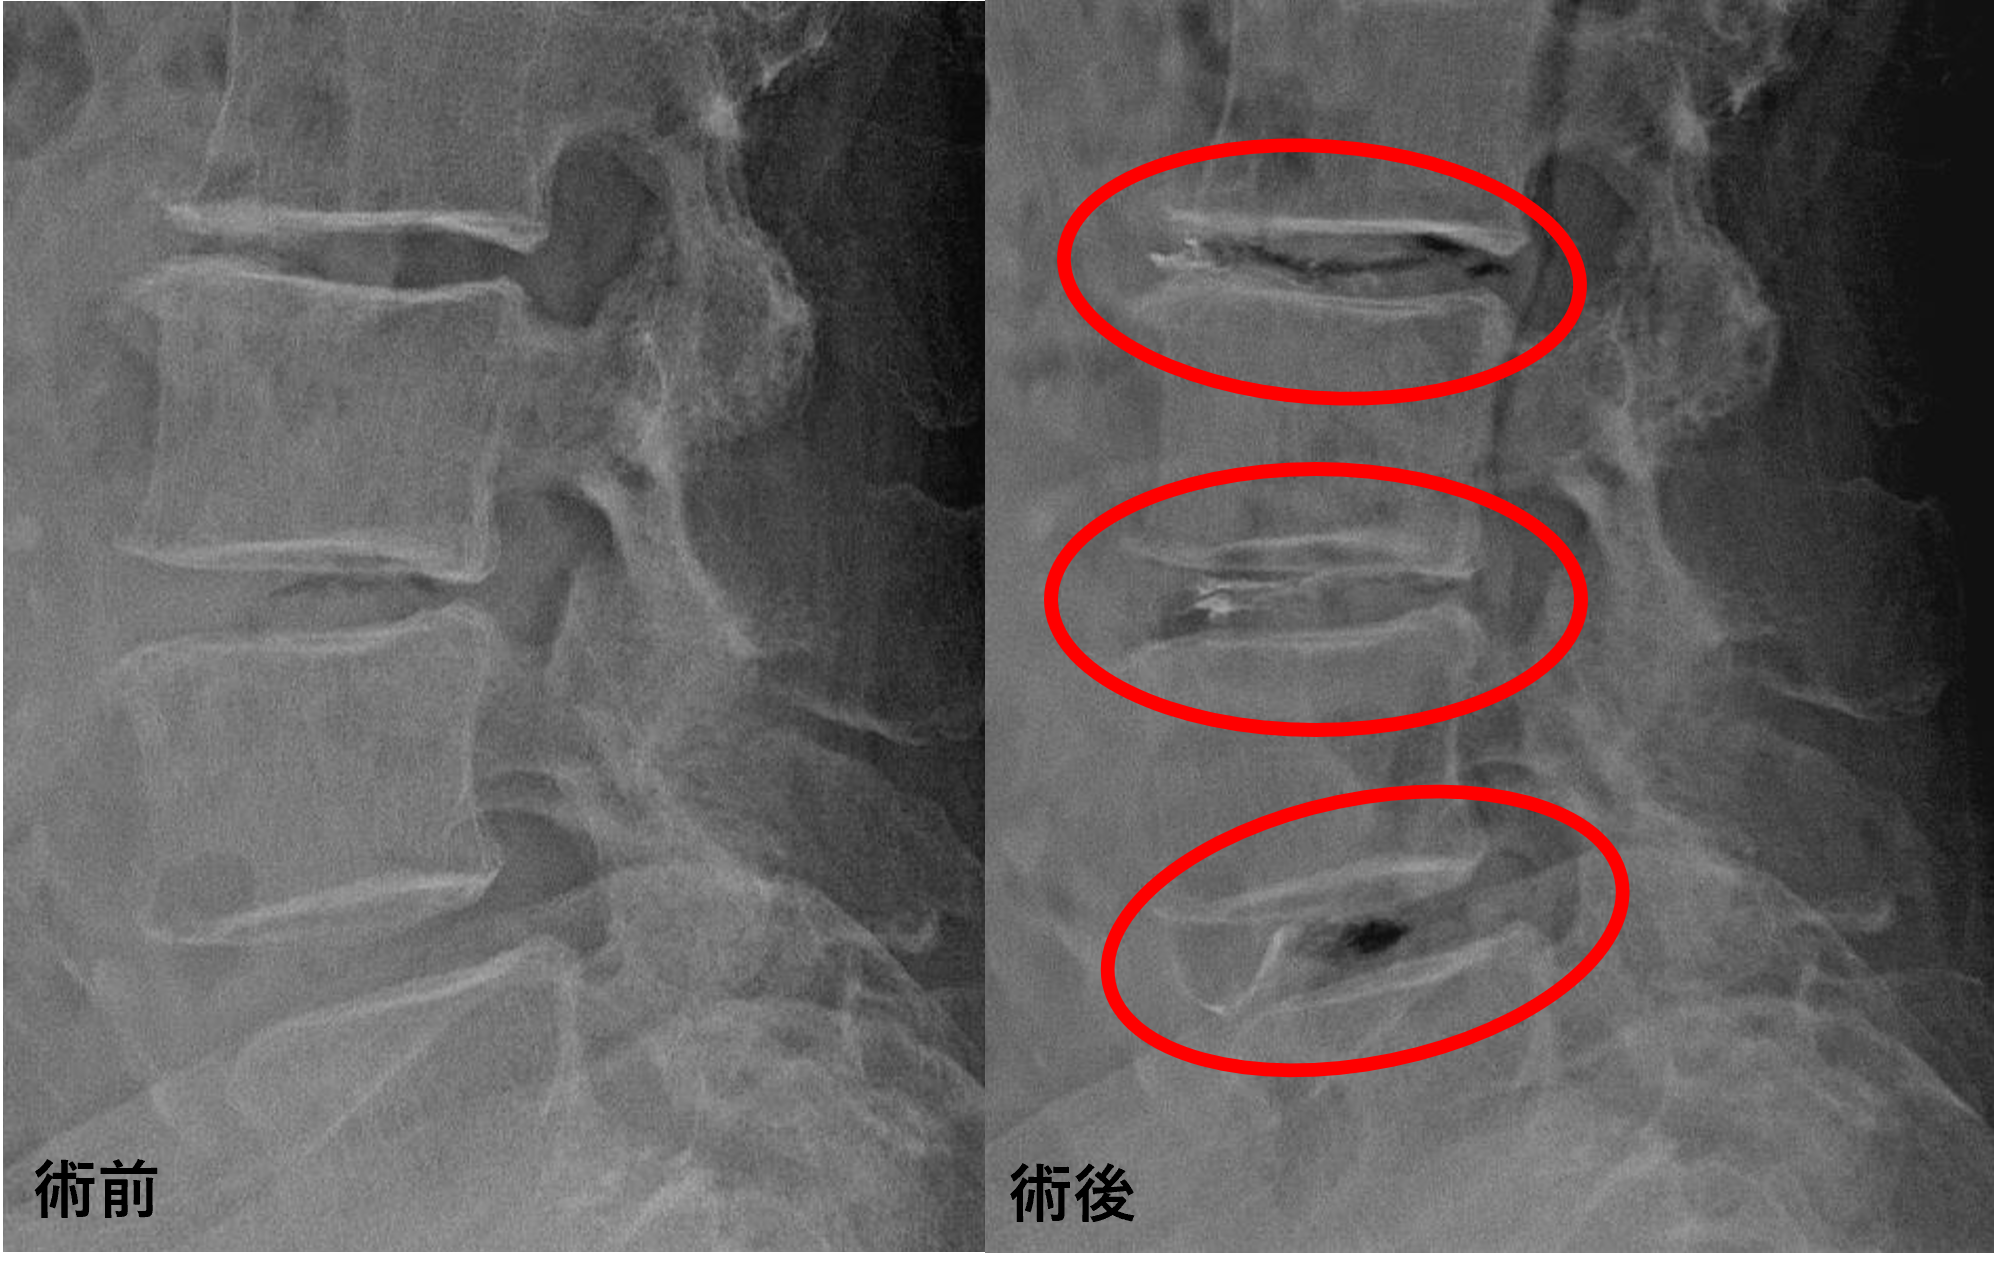

画像及び所見について

• L2/3 – 椎間板変性、膨隆、椎間孔狭窄

• L3/4 – 椎間板変性、膨隆、椎間孔狭窄、脊柱管狭窄

• L4/5 – 椎間板変性、膨隆、椎間孔狭窄、脊柱管狭窄、変性すべり

• L5/s – 椎間板変性、骨癒合

以上のことが画像上認められました。

L2/3、3/4、4/5の椎間板所見による脊柱管の圧排が、症状の原因の可能性が高い。

患者様と相談の元、L2/3、3/4、4/5にセルゲル法を施行